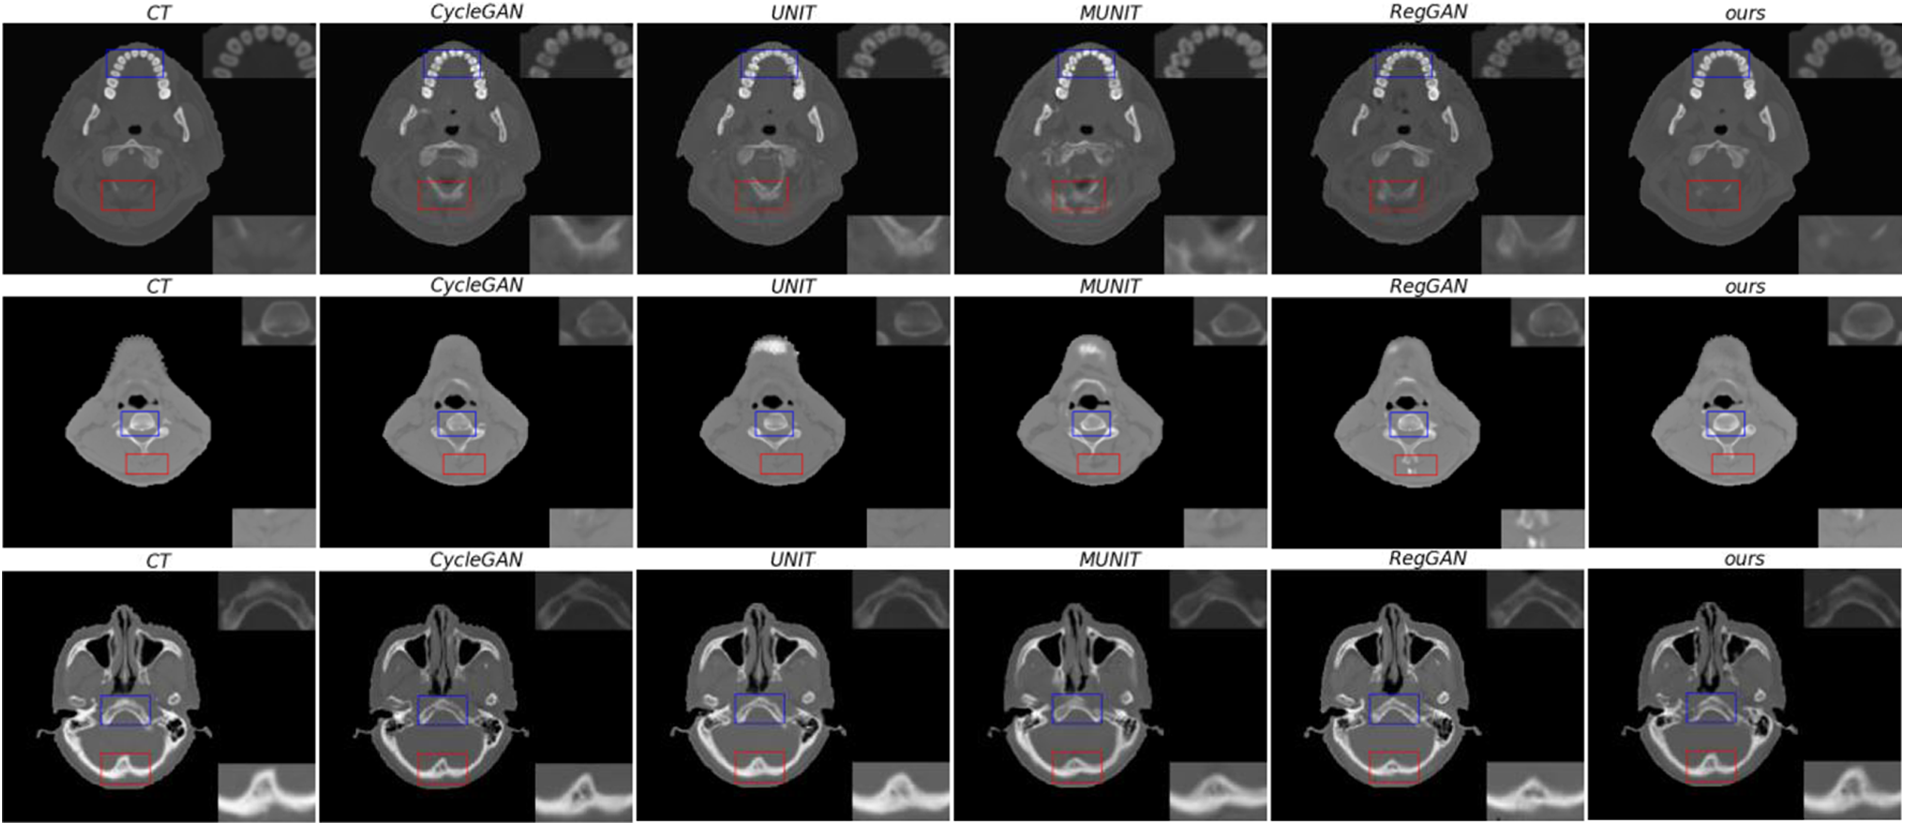

Through qualitative comparison, it is further illustrated that the anatomical structure of the sCT synthesized by this method is more similar to the genuine CT. In Fig. 7, the real CT and corresponding sCT images randomly selected by the proposed model are shown. In the figure, the areas marked by the blue and red boxes are enlarged, which are located in the upper right corner and the lower right corner of the image, respectively. In the figure, this research visually compares the synthetic quality of sCT images of bones. In the comparison of three sets of images, the proposed method outperforms the other four methods in terms of the quality of synthetic images in bone tissues. At the same time, it has advantages in synthesizing some texture details, such as the red-marked area of the first group of images. This shows that the proposed method can transform MR image mode into its sCT corresponding mode more effectively.

Figure 7: From left to right, there are genuine CT, sCT synthesized by CycleGAN, sCT synthesized by UNIT, sCT synthesized by MUNIT, sCT synthesized by RegGAN, and sCT synthesized by the proposed method. The upper right corner of the image is a locally enlarged image of bones or tissues in a blue frame, and the lower right corner o is a locally enlarged image of bones or tissues in a red frame